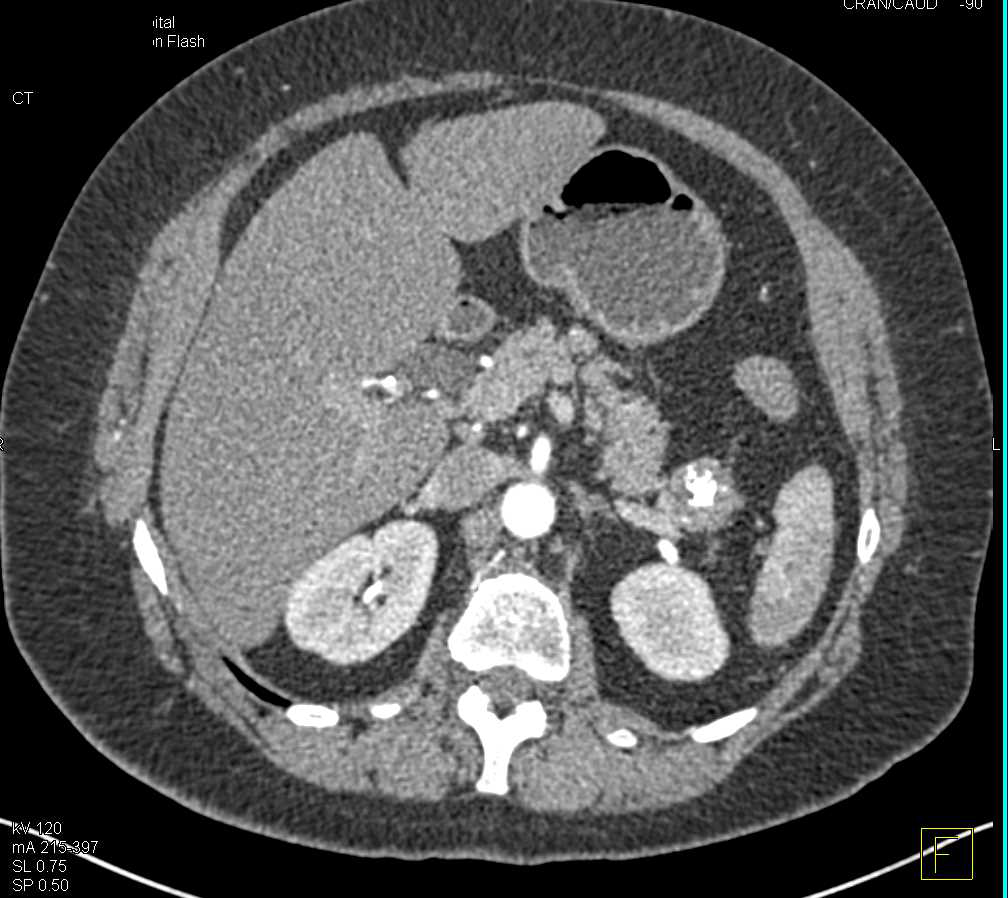

Lymphoepithelial Cyst Tail of Pancreas and Splenic Hemangiomas